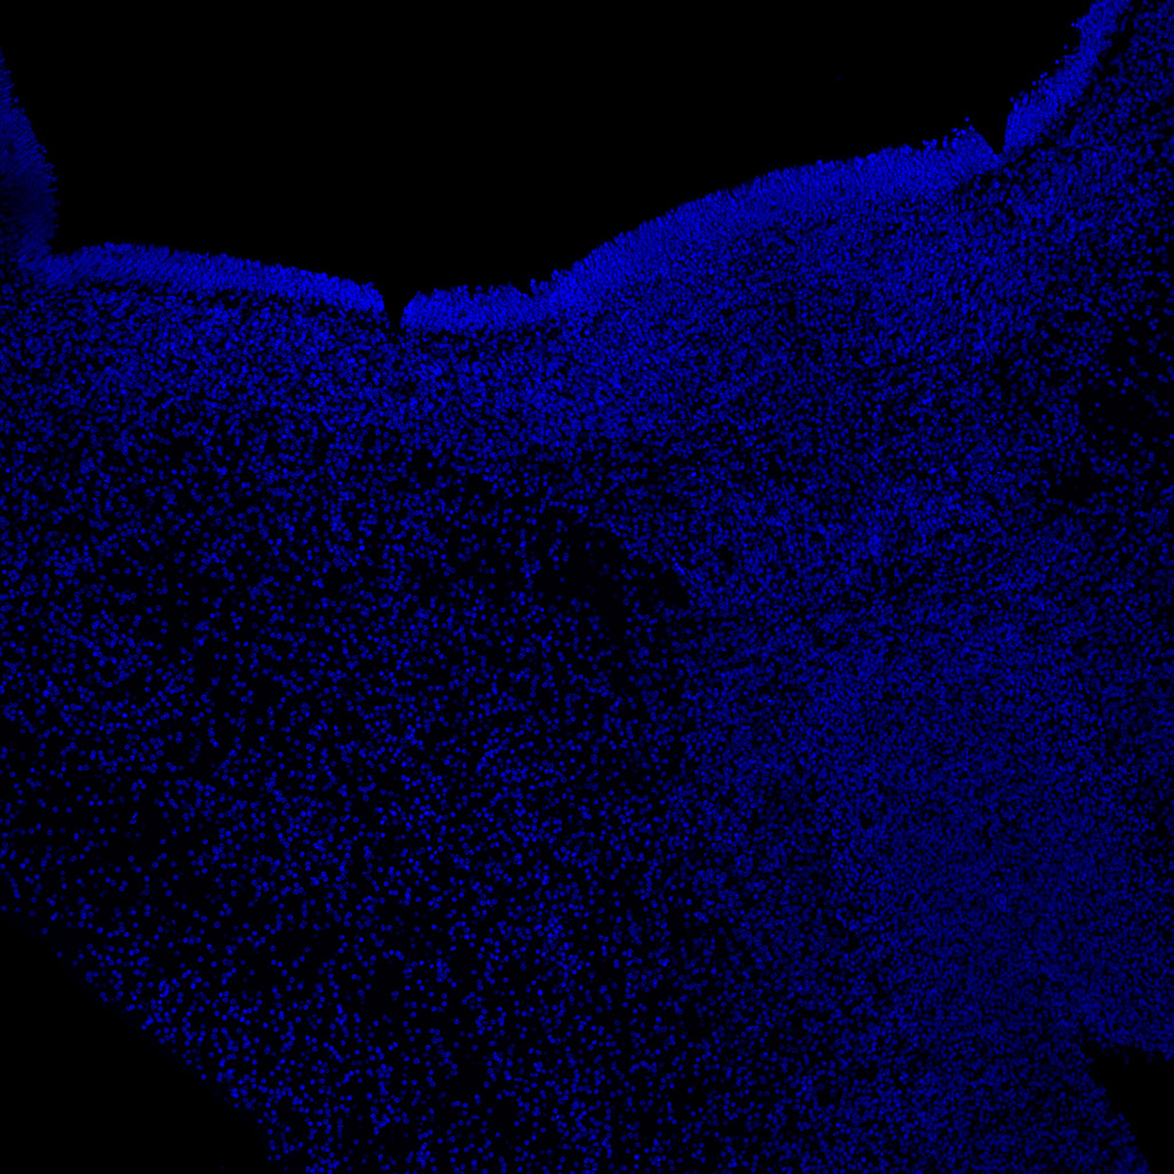

KI67

6PCW human midbrain